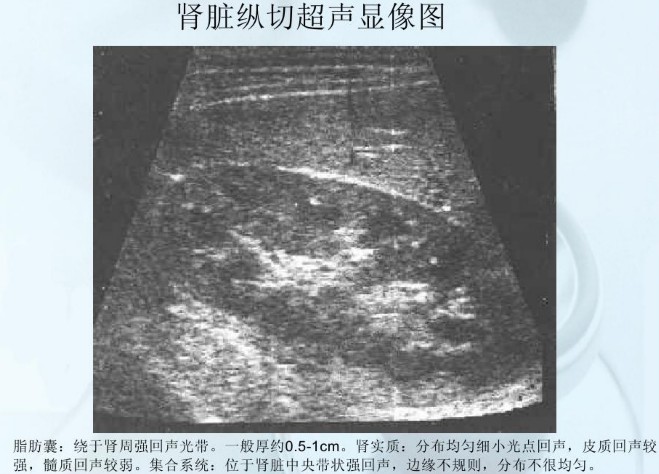

肾脏的形态像一颗蚕豆,内侧呈袋状向内凹,像一个钱包,称为肾窦(Renal sinus)。肾实质包绕肾窦,超声上显示肾实质光点亮度较低,肾窦光点亮度明显增高,位于中央呈椭圆形,内包括肾盂(Renal pelvis)、肾盏(Renal calyx)、血管等。肾盂、肾盏与输尿管(Ureter)相通。